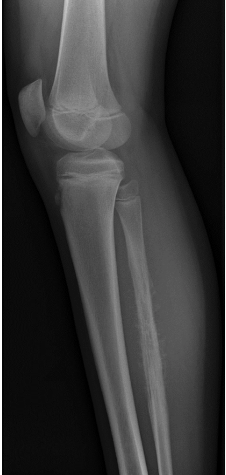

Osteossarcoma

- Perfil: É o mais comum (60% dos tumores ósseos). O pico ocorre na segunda década, durante o estirão da puberdade.

- Localização: Metáfise de ossos longos, principalmente fêmur distal e tíbia proximal (região do joelho).

- Clínica: Apresentação localizada. Dor persistente e progressiva, aumento de volume e sinais flogísticos locais (calor e eritema).

- Diagnóstico: RX ósseo com imagem característica de “raios de sol” (sunburst). O principal sítio de metástase é o pulmão.

Sarcoma de Ewing

- Perfil: Tumor raro, também com pico na $2^{a}$ década. 50% ocorrem no esqueleto axial.

- Clínica: Apresentação sistêmica. Além da dor localizada, cursa com emagrecimento, febre e anemia.

- Diagnóstico: RX ósseo com achado típico de “casca de cebola” (onion skin). Requer estadiamento completo, incluindo mielograma/biópsia de medula óssea.